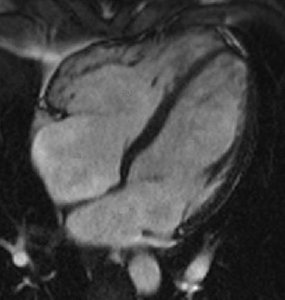

Takotsubo cardiomyopathy is an acute, reversible cardiac syndrome often triggered by emotional or physical stress. It is more prevalent in women and is characterized by transient left ventricular dysfunction, typically involving the apex (apical ballooning).

Imaging: Apical akinesis with preserved basal contraction

Imaging | Dilated chambers, thin walls | Apical akinesis, ballooning |